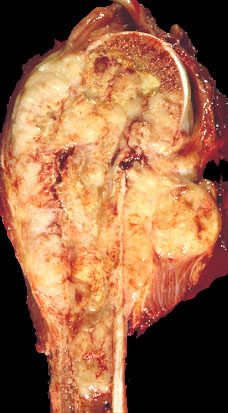

Gross description

- Gray-tan mass with infiltrative borders (Semin Diagn Pathol 2014;31:39)

- Intramedullary mass with soft tissue involvement

- Areas of hemorrhage and necrosis frequent

- Assess chemotherapy induced necrosis (≥ 90% good) with mapping

Gross images